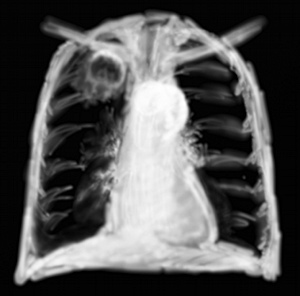

RP pneumonie basale du poumon droit

Les pneumonies alvéolaires peuvent commencer lentement en donnant un simple voilage d’un lobe ou d’un segment, et le bronchogramme peut être difficile à voir comme dans l’exemple 2. D’autant plus que ce n’est pas un lobe supérieur qui est touché mais un lobe inférieur. On citera la classique pneumopathie d’inhalation qui se développe dans le lobe inférieur droit pour une question de quasi verticalité de la bronche inférieure droite.